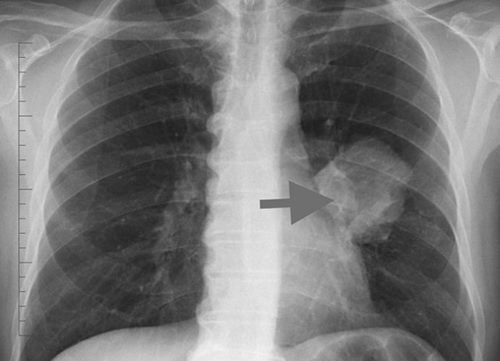

Як повідомляє Головне управління Держпродспоживслужби у Чернівецькій області, на Буковині на чверть зросла кількість випадків захворювання на туберкульоз порівняно з минулим роком. Опублікувавши офіційний звіт, управління наголосило, що найвища кількість зафіксованих проблем з органами дихання по області у Сторожинецькому, Путильському та Хотинському районах. Далі на ichernivchanyn.

У Чернівецькій області торік кількість хворих на туберкульоз дихальних шляхів зросла майже на 25%. Це випливає із звіту Головного управління Державної служби України з питань безпечності харчових продуктів та захисту споживачів про оздоровчо-епідеміологічну ситуацію на Буковині. Зі звіту стає ясно, у 2019 році зафіксована тенденція до збільшення захворюваності на туберкульоз дихальних шляхів порівняно з 2018 роком. Рівень захворюваності збільшився на 24,1%, з них 26,5% випадків було підтверджено та зареєстровано офіційно. Ця кількість більшою мірою вирахувана по статистиці Сторожинецького, Путильського та Хотинського районів.